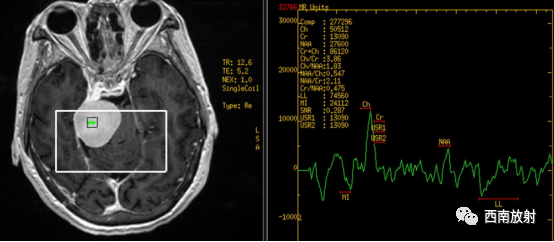

▲病例:脑膜瘤。本病女性,肿瘤信号呈等T1等T2信号,DWI等信号,ADC图信号不高,软组织信号增强扫描明显强化,强化均匀,并见脑膜尾征。波谱成像:NAA波峰较低,因此提示病变来源脑外,不含神经元标记物,提示非神经元的脑肿瘤。显示LL峰明显升高,Cr不形成波峰,而Cho位置较低。病灶MI峰由下方转到0线上。